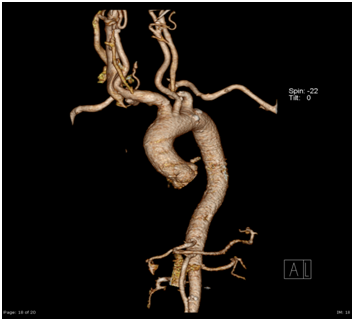

ENT referral was sought and a colour Doppler was advised which showed an abnormal large artery in running across in front of the Trachea. A CT angiography was then done which revealed anomalous Brachiocephalic trunk running from left to right across in front of the trachea which had pushed the thyroid gland to the level of Cricoid cartilage (Figures 1-4).

Figure 1 Angiogram.

Figure 2 Angiogram.

Figure 3 Angiogram

Figure 4 VRT, CT Angiography

Literature was searched for this anomaly and it was found to be a rare anomaly (Beautiful description in an anatomy journal).4 The challenges were two: first, the surgical difficulty in view of the horizontally running large vessel in front of the trachea just 1cm below the Cricoid cartilage and second, the risk of post operative hemorrhage due to the vessel hitting against the Tracheostomy tube due to pounding pulsations, movement of the tube due to mechanical ventilation, frequent handling for suctioning and dressing and neck movements.5-7

The brachiocephalic artery (or brachiocephalic trunk or innominate artery) is an artery of the mediastinum that supplies blood to the right arm and the head and neck. It is the first branch of the aortic arch, and soon after it emerges, the brachiocephalic artery divides into the right common carotid artery and the right subclavian artery. There is no brachiocephalic artery for the left side of the body. The left common carotid and the left subclavian artery, come directly off the aortic arch. However, there are two brachiocephalic veins. It arises, on a level with the upper border of the second right costal cartilage, from the commencement of the arch of the aorta, on a plane anterior to the origin of the left carotid; it ascends obliquely upward, backward, and to the right to the level of the upper border of the right sternoclavicular articulation, where it divides into the right common carotid and right subclavian arteries. The artery then crosses the trachea in front of it obliquely from the left to the right, roughly at the middle of the trachea or the level of the ninth tracheal cartilage.